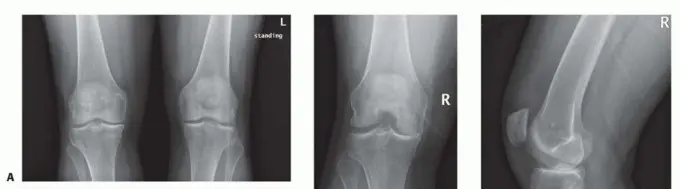

- الأشعة السينية قبل الجراحة: تشمل الأشعة السينية التي تُجرى مع تحمل الوزن (AP)، والأشعة السينية الجانبية في منتصف الثني (PA)، والأشعة الجانبية (Lateral)، والأشعة السينية للرضفة (Skyline patellar views). هذه الفحوصات ضرورية لتقييم محاذاة المفصل الفخذي الساقي وحالة الحجرات المتبقية من الركبة.

الشكل 1 • صور الأشعة السينية قبل الجراحة. أ. منظر أمامي خلفي يوضح تضيق المساحة المفصلية الأنسية للركبة اليمنى وتشوهًا تقوسيًا. ب. منظر خلفي أمامي. ج. منظر جانبي يوضح الحفاظ على المساحة المفصلية الخلفية الفخذية الساقية. د. منظر علوي للرضفة.

- نتائج الأشعة السينية لالتهاب المفاصل أحادي الحجرة: قد تشمل تضيق المساحة المفصلية، تصلب تحت الغضروف وتغيرات كيسية، نتوءات عظمية، واختلال في محاذاة الطرف السفلي المتأثر.